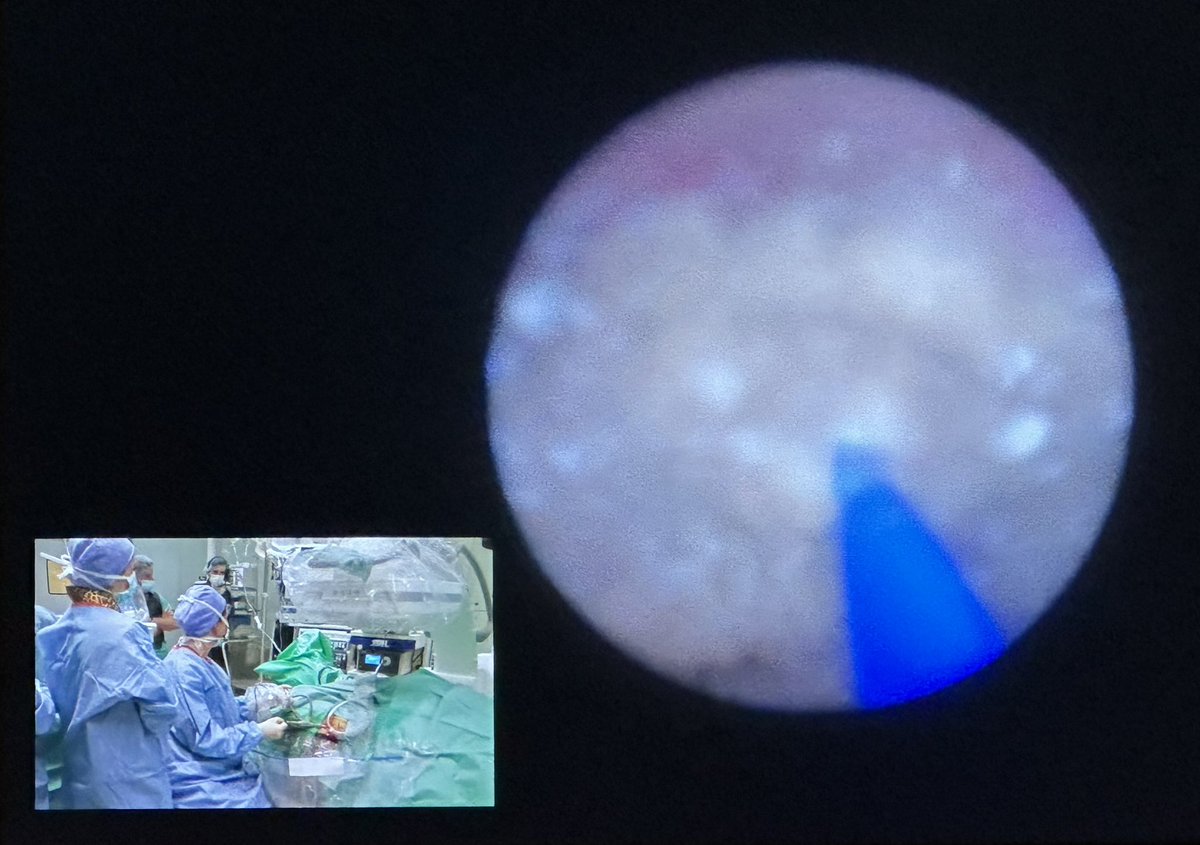

Guido Giusti@GuidoGiusti·

Always rewarding watching ur fellows acquiring endo skills as @urommoo performing SOLO #RIRS 👏🏻BRAVA Mon Mon! Proud of ur dedication to #ETCE! PS: after #AUA23 successes, in the background u can see the Boss back to normal life moving the C-arm according to Mon Mom commands!😂